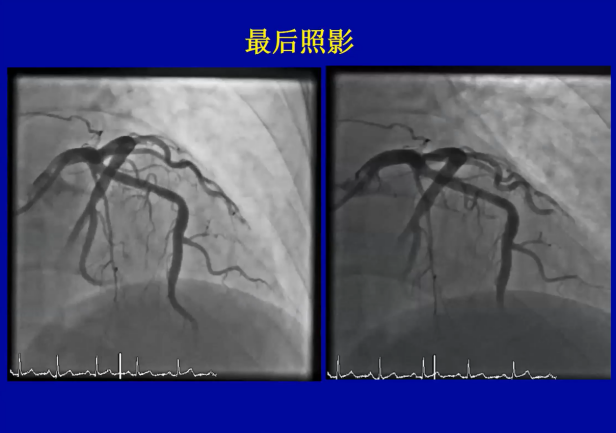

陈韵岱教授分享了两例高难度复杂钙化病变应用Shockwave IVL预处理的精彩病例,这两例钙化病变程度严重,腔内影像学评估可见较厚的钙化环,非顺应性球囊高压扩张无法打开钙化环,但均在Shockwave IVL治疗后成功植入支架,后扩张后获得了满意的即刻手术效果,彰显了Shockwave IVL在一般预处理手段“束手无策”时的独特价值。

病例1

病例2